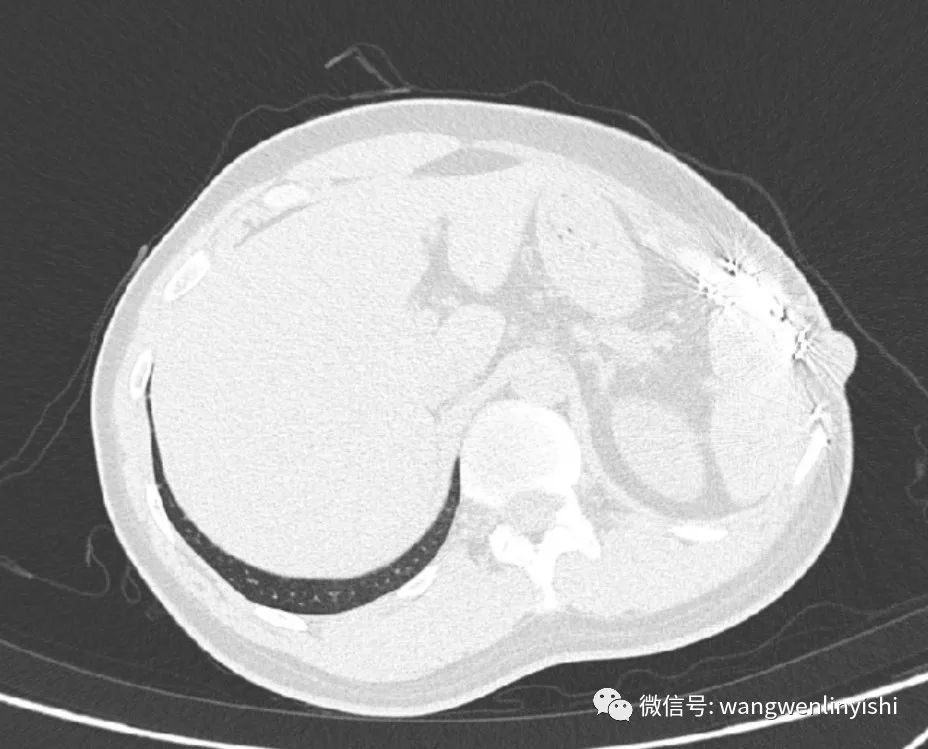

入院查体: 左侧胸壁可见手术疤痕,切口中部可见复发的肿瘤,大小约5X5CM。影像学检查提示肿瘤局限于切口处,位置表浅,深部及身体其他部位无转移。

(CT检查提示复发肿瘤位置)